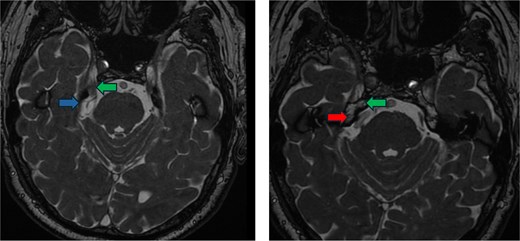

AR visualization of the 3D model demonstrated a laterally and superiorly deviated vertebrobasilar junction with a compressive dolichoectatic and atherosclerotic elbow of the right vertebral artery causing compression as it traversed underneath the trigeminal nerve root entry zone (Fig. 1). A downward-looping superior cerebellar artery was also compressing the nerve from above. In the operating room, the AR system was used to register the 3D model onto the patient’s head, which allowed us to plan the incision and craniotomy location in a more individualized manner and to optimally position the patient for a more ergonomic operation (Fig. 2 and Video 1). The AR overlay displayed the underlying transverse–sigmoid junction, allowing a more accurate burr hole placement. There was a loop of the superior cerebellar artery which was compressing the nerve superiorly at the root entry zone. The vertebral artery was identified. We created a sling with a 4-0 Nurolon suture wrapping around the vertebral artery and suturing it to the dura inferiorly (Video 2). Teflon pledgets were then used to pad the nerve and it was now completely decompressed from the vascular structures. Postoperative MRI of the brain showed effective decompression of the trigeminal nerve (Fig. 3).

Postoperative imaging. FIESTA scan demonstrating the relief of compression of the trigeminal nerve (green arrow) by the vertebral artery (red arrow) and the superior cerebellar artery (blue arrow).